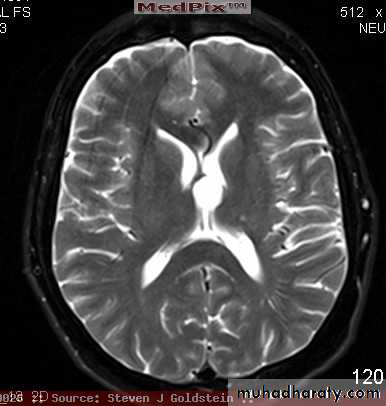

arise from the epidermal lining of the ventricular system, usually whitish in color & can lead to early hydrocephalusCT scan of all gliomas shows usually hyperdense lesion, irregular in shape, surrounded by edema & may be enhanced with or without cystic degeneration.

( CORONAL MRI )

Note: all gliomas are dealt with by surgical intervention ,by excision of the tumor followed by radiotherapy , but prognosis is not very good & fluctuates from 5 years survival of less than 5% in Glioblastoma multiformis to up to 100% 5 years survival in Oligodendroglioma treated by surgery & successive radiotherapy.